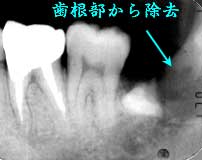

初診時 パノラマ 術中 Dental写真

歯冠部分の除去ができず、歯根部分から除去

元々開口が小さい上に、歯冠上部が崩壊し術野の確保が困難で難航を極めた抜歯であった。 残存した歯冠下部の先端は歯槽骨に食い込む形で、歯冠カットしたのちも通常の方法では除去 不可能なまま時間が経過。やむを得ず比較的単純な形態をした歯根部分から抜歯して、最終的に 何とか残った歯冠下部を除去して抜歯を終了(所用時間:1時間以上)。

通常の水平埋伏だと、ほとんど15分以内に終了させる自信はあり1時間以上の抜歯は 数年に1度程度しか遭遇しない。本症例では、術野の確保が困難であったこと以上に、 歯冠下部の咬頭が歯槽骨に食い込んでいたことが抜歯を困難にした最大の理由だった と考えられる。そのことは、術前のレントゲンでも読み取ることは可能だったと思われるが、 現実には、術中の手ごたえとDental写真を見て始めて実感として読み取ることができた。